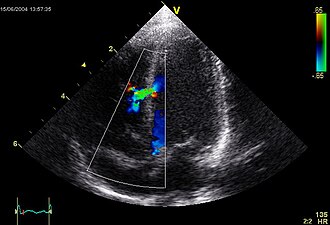

Ehokardiografija je skupina neinvazivnih pretraga srca ultrazvukom. Temelji se na registraciji ultrazvučnih valova što ih reflektiraju srčane strukture. Ehokardiografija je dominantna metoda kardiološkog pregleda koja, pouzdanim podatcima, najčešće otklanja potrebu za invazivnim pretragama srca. Daje ključne podatke za dijagnozu: funkcijske parametre, točne mjere srčanih šupljina i debljine stijenki, oblik srčanih struktura, vrijednosti intrakardijalnih tlakova, procjenu težine bolesti srčanih zalistaka i drugo. Jednodimenzijska ehokardiografija (M-prikaz, od eng. motion: kretanje) prikazuje gibanje srčanih struktura s pomoću jednoga piezoelektričnoga kristala i daje najbolji vremenski prikaz zbivanja u srcu. Dvodimenzijska ehokardiografija daje slojevne slike srčanih struktura u "živoj slici" s dobrom prostornom orijentacijom. Dopplerova ehokardiografija primjenjuje se osobito u dijagnostici prirođenih i stečenih bolesti srca. [1]

Ultrasonografija ili ehosonografija (lat. sonus: glas, zvuk) je upotreba ultrazvuka u dijagnostičke svrhe. Izvor ultrazvuka prisloni se na tijelo, a reflektirani signali ultrazvučnih valova prikazuju se na zaslonu osciloskopa. Na osnovi različite akustične gustoće mogu se prikazati različne strukture (tkiva, organi) u tijelu. Dvodimenzionalni sustav na Dopplerovu učinku (takozvani kolor dopler) omogućuje procjenu protoka krvi u žilama određenog područja. Ehosonografija je našla obilnu i korisnu primjenu u ginekologiji, porodništvu (praćenje razvoja čeda u maternici, rano otkrivanje nepravilnosti), u kardiologiji (ehokardiografija), neurologiji (ehoencefalografija), oftalmologiji (ehooftalmografija) i drugdje. [2]